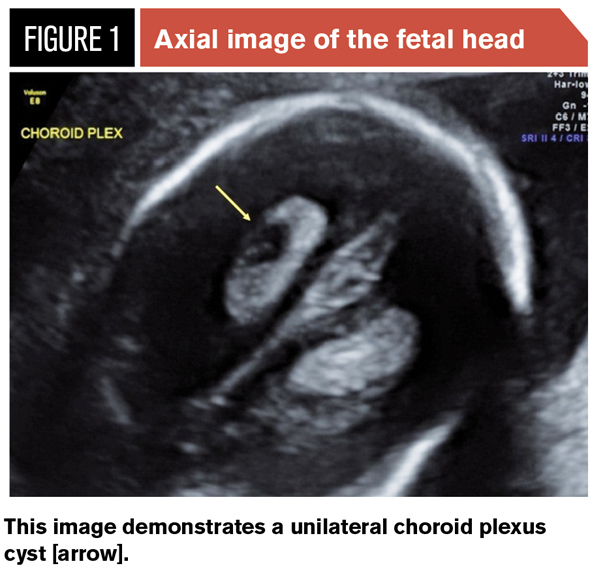

We were so thankful to learn that Baby Clough’s measurements are right on track and that baby has no birth defects, but unfortunately, we also received some minor negative news. During the ultrasound, they noticed a pocket of water in one of the ventricles of baby’s brain. This pocket of water is called a Choroid Plexus Cyst. Although the cyst is not dangerous to a baby and often times disappears all on its own, it can be an indicator of a much more serious condition called Trisomy 18. Trisomy 18, also called Edwards Syndrome, is a genetic disorder where the baby has three copies of chromosome 18. This extra copy causes many of the baby’s organs to develop abnormally. Common problems associated with Trisomy 18 can be a very small baby, with heart defects, kidney problems, excess amniotic fluid, small head size, deformed hands and feet, and more. Because most Trisomy 18 babies have several health conditions, studies show that most cases are fatal, with life generally ended before the baby is even born.

We were so thankful to learn that Baby Clough’s measurements are right on track and that baby has no birth defects, but unfortunately, we also received some minor negative news. During the ultrasound, they noticed a pocket of water in one of the ventricles of baby’s brain. This pocket of water is called a Choroid Plexus Cyst. Although the cyst is not dangerous to a baby and often times disappears all on its own, it can be an indicator of a much more serious condition called Trisomy 18. Trisomy 18, also called Edwards Syndrome, is a genetic disorder where the baby has three copies of chromosome 18. This extra copy causes many of the baby’s organs to develop abnormally. Common problems associated with Trisomy 18 can be a very small baby, with heart defects, kidney problems, excess amniotic fluid, small head size, deformed hands and feet, and more. Because most Trisomy 18 babies have several health conditions, studies show that most cases are fatal, with life generally ended before the baby is even born.

Fortunately, our Doctor is not overly concerned about the cyst and it having any correlation to our baby possibly having Trisomy 18. He made us aware that many healthy babies develop a Choroid Plexus Cyst without also having Trisomy 18. These babies go on to have a successful pregnancy and birth and live a healthy normal life. The chances of a baby being diagnosed with Trisomy 18 is roughly 1 out of 2000, but since our baby has no indications of any birth defects that risk is even lower. The odds do seem to be in our favor and I am confident that Baby Clough #3 is extremely healthy, but a small part of me can’t seem to shake the fear that maybe we aren’t going to be so lucky. Statistics are no longer just statistics and even the ones with good margins don’t provide as much hope as they use to. Less than 1% of babies are delivered stillborn, the odds of us ever losing Emilia were slim, but we still lost her.